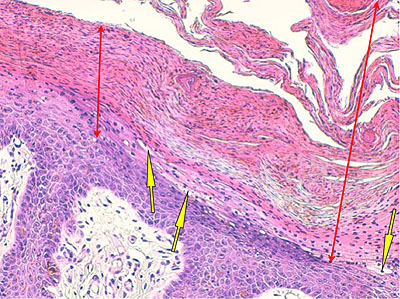

Photo 2 (Hémalun Eosine X 40) : au faible grossissement, l’épiderme revêt un aspect bleu-blanc-rouge,

bleu pour hyperplasie des couches basales, blanc pour vacuolisation des acanthocytes sous-cornés et

rouge pour parakératose de la couche cornée. Le derme est faiblement à modérément inflammatoire.

Légendes de la Photo 2 :

- Flèche bleue : hyperplasie des couches basales

- Flèche blanche : vacuolisation des acanthocytes sous-cornés

- Flèche rouge : pour parakératose de la couche cornée

- Étoile rouge : Le derme est faiblement à modérément inflammatoire

Photo 3 (Hémalun Eosine X 100) : aspect bleu-blanc-rouge à plus fort grossissement,

bleu pour hyperplasie des couches basales, blanc pour vacuolisation des acanthocytes

sous-cornés et rouge pour parakératose de la couche cornée. Le derme superficial est

le siège d’un infiltrat inflammatoire mononucléé périvasculaire modéré.

Légendes de la Photo 3 :

- Flèche bleue pour hyperplasie des couches basales

- Flèche blanche pour vacuolisation des acanthocytes sous-cornés

- Flèche rouge pour parakératose de la couche cornée

- Étoile rouge : Le derme est faiblement à modérément inflammatoire